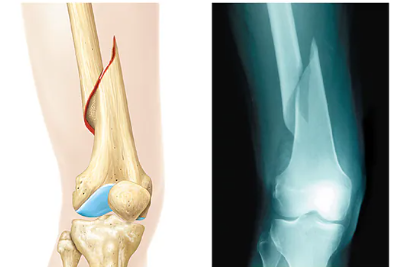

Compression